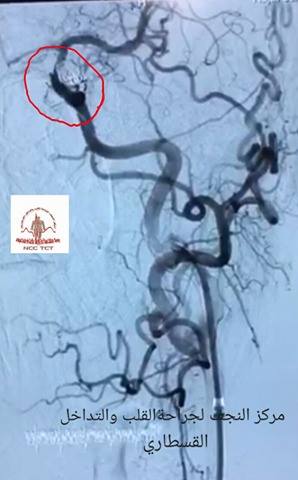

اجرى مركز النجف الاشرف لجراحة القلب والتداخل القسطاري عملية قسطرة معقدة لغلق شريان (ام الد الماغي). وقال مدير المركز والمشرف على العملية الدكتور خالد ابراهيم عنبر لوكالة نون ان العملية تتميز عن سابقاتها كونها تمت بتقنية الطرح الرقمي (DSA) كما انها اكثر تعقيدا من العمليات المماثلة التي اجراها المركز منذ سنوات عديدة موضحا ان مدخل (ام الدم) كان عريض ويحتاج الى تداخل جراحي مضيفا ان عملية التداخل القسطاري تمت بنجاح كبير مشيدا بجهود كادر مركز النجف لأمراض القلب والتداخل القسطاري وتميزه الدائم ومشيرا الى ان المركز اجرى خلال العام الماضي 6000 عملية تداخل قسطاري مع العديد من التداخلات الجراحية الدقيقة وكان آخرها رفع ورم يبلغ حجمه 5*10 سم من الاذين الايسر لشاب في 24 من العمر.